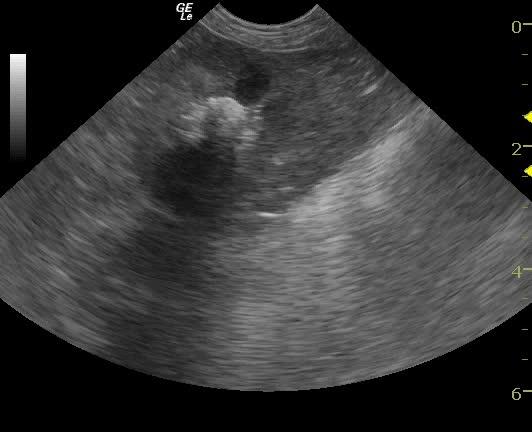

An 11-year-old SF Bichon dog was presented with a history of 3-4 days of lethargy, anorexia, and vomiting. Abnormalities on physical examination were tense abdomen, mild dehydration, and moderate dental tartar. Urinalysis (free-flow sample) showed inappropriate SG, (1.017), hematuria, and, pyuria. Abnormalities on CBC and serum biochemistry were leukocytosis, monocytosis, neutrophilia, azotemia, and hyponatremia.